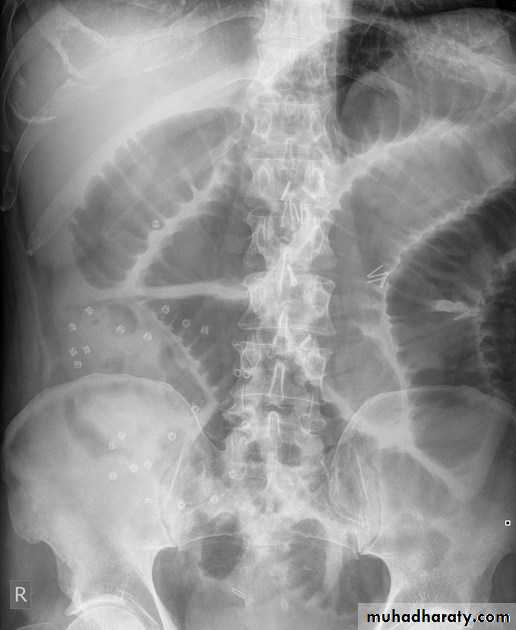

Small bowel obstruction accounts for 80% all mechanical intestinal obstruction; the remaining 20% result from large bowel obstruction

Radiographic features

Abdominal radiograph

Abdominal radiographs are only 50-60% sensitive for small bowel obstruction .

In most cases, the abdominal radiograph will have the following features:

dilated loops of small bowel proximal to the obstruction

predominantly central dilated loops

three instances of dilatation over 3 cm

valvulae conniventes are visible

fluid levels if the study in erect position

Large bowel obstruction (LBO) are often impressive on imaging, on account of the ability of the large bowel to massively distend. This condition requires prompt diagnosis and treatment

Colonic distension > small bowel

Peripherally located

Dilated loops Less in no. than SBO

Presence of haustra